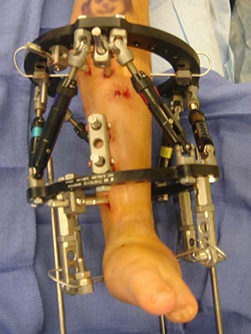

If the patient is undergoing lengthening for fibular hemimelia, then a Taylor spatial frame (TSF) external fixator is used. During the lengthening phase, the patient or parent adjusts the TSF on a daily basis to perform the lengthening and deformity correction. The patient is seen every two weeks for clinical and X-ray examination here at the International Center for Limb Lengthening (ICLL) in Baltimore, Maryland.

Emma wearing an external fixator in the pool.Typically the patient is admitted to the hospital on the day of the lengthening surgery. A circular external fixator is placed on the lower leg and foot of the involved side. The type of external fixator used is usually the TSF. The foot is always included in the TSF to ensure stability of the ankle joint and to maintain the proper foot position during the distraction or lengthening phase of the treatment. The tibia is cut through one or two small incisions after the TSF is applied. The TSF stabilizes the cut bones and maintains alignment.